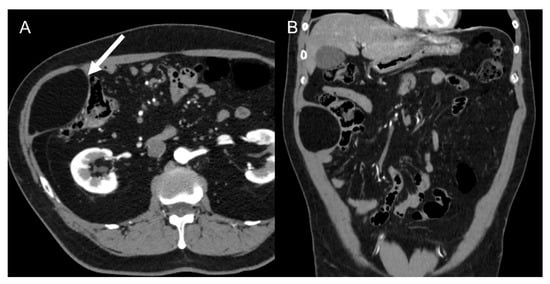

- Dedifferentiated liposarcomas (Figure 2) are high-grade tumors with poor prognosis. Characteristic features include heterogeneous nonlipomatous mass within, adjacent to, or surrounding a fatty mass [37,38]. There may be no evidence of fat-density tissue in up to 20% of cases, making the imaging diagnosis difficult [40]. Enhancing septa within the fatty portions are frequently seen [37]. Calcifications are rare (around 25% of cases) and are poor prognostic factors [39].

Figure 2. Dedifferentiated retroperitoneal liposarcoma in a 68-year-old man. Axial (A) and coronal (B) contrast-enhanced CT images in the venous phases show a 24 cm solid mass in the right retroperitoneal space, with internal necrotic areas and adjacent nodules (arrows). The lesion was histologically confirmed at biopsy.